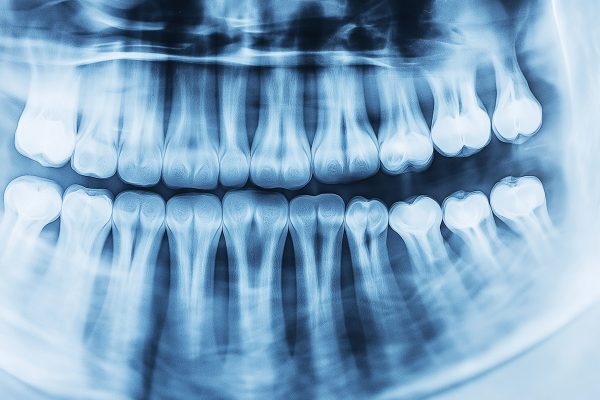

Imagerie Dentaire